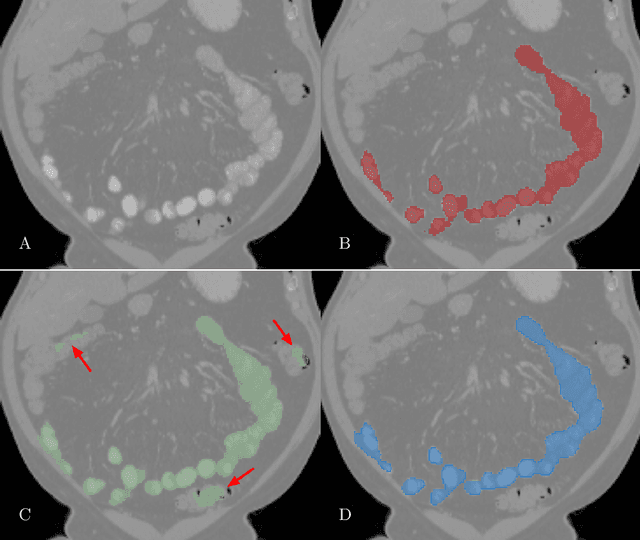

Abstract:We present a novel unsupervised domain adaptation method for small bowel segmentation based on feature disentanglement. To make the domain adaptation more controllable, we disentangle intensity and non-intensity features within a unique two-stream auto-encoding architecture, and selectively adapt the non-intensity features that are believed to be more transferable across domains. The segmentation prediction is performed by aggregating the disentangled features. We evaluated our method using intravenous contrast-enhanced abdominal CT scans with and without oral contrast, which are used as source and target domains, respectively. The proposed method showed clear improvements in terms of three different metrics compared to other domain adaptation methods that are without the feature disentanglement. The method brings small bowel segmentation closer to clinical application.